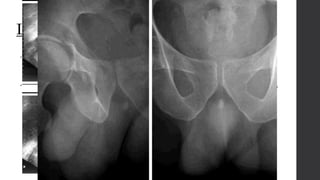

TC: Detecta cálculos de1 mm de diámetro, visualizar los datos secundarios a la obstrucción como son: • Hidrouréter • Hidronefrosis • Edema renal y periureteral • Engrosamiento de la grasa perinefrítica • Aumento de tamaño del riñón afectado TC Contrastada Cálculos radiolúcidos, radiopacos, hidronefrosis o ambos.